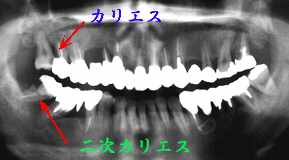

一連の歯周処置と補綴処置を終えメインテナンスに移行して順調に経過していたように 思われたが、レントゲンを撮って始めてカリエスの存在に気づいた

考察:

メインテナンス時には必ず脱離やカリエスのチェックを行っていた積もりですが、カリエスの 存在に全く気がつきませんでした。まだ何とかなる時点での発見に安堵する反面、それまで 気がつかなかったことに情けない思いを抱いています。智歯であるが故に発見が遅れたと いうのは言い訳、智歯であるからこそもっと注意しておくべきでした。

感想:

3年でこれだけのカリエスはちょっと異例です。気の緩みがあったわけではありませんが ショックは大きい!!